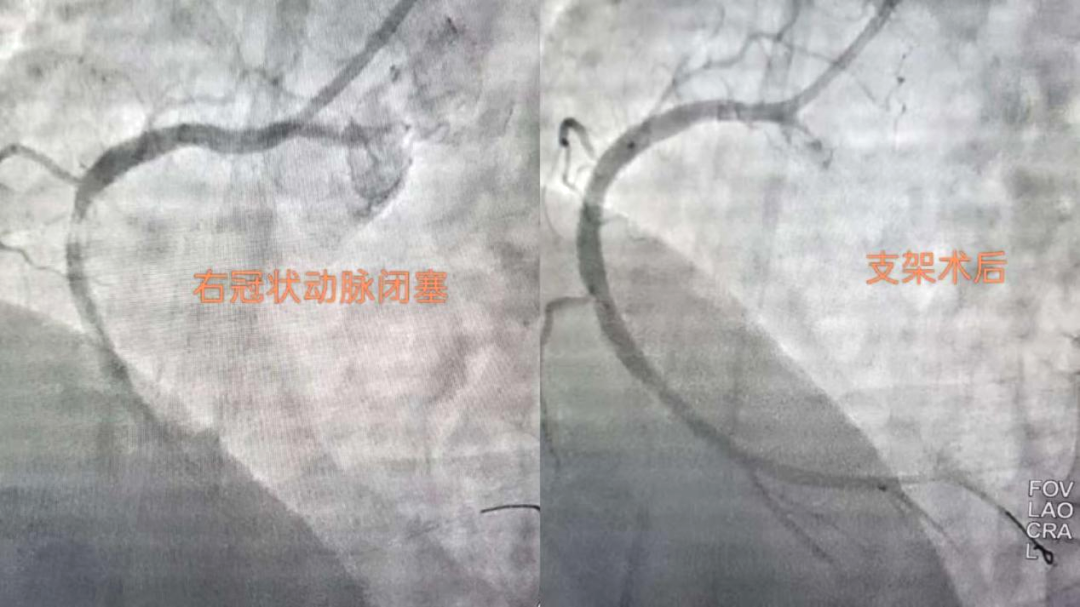

抢时间就是抢生命!06:46穿刺,06:47成功,06:49冠脉造影明确:右冠状动脉中段完全闭塞。导丝迅速通过,支架精准植入,07:03血流恢复,手术成功结束。患者胸痛明显缓解,生命体征趋于平稳。从入院到血管再通,不到两小时。